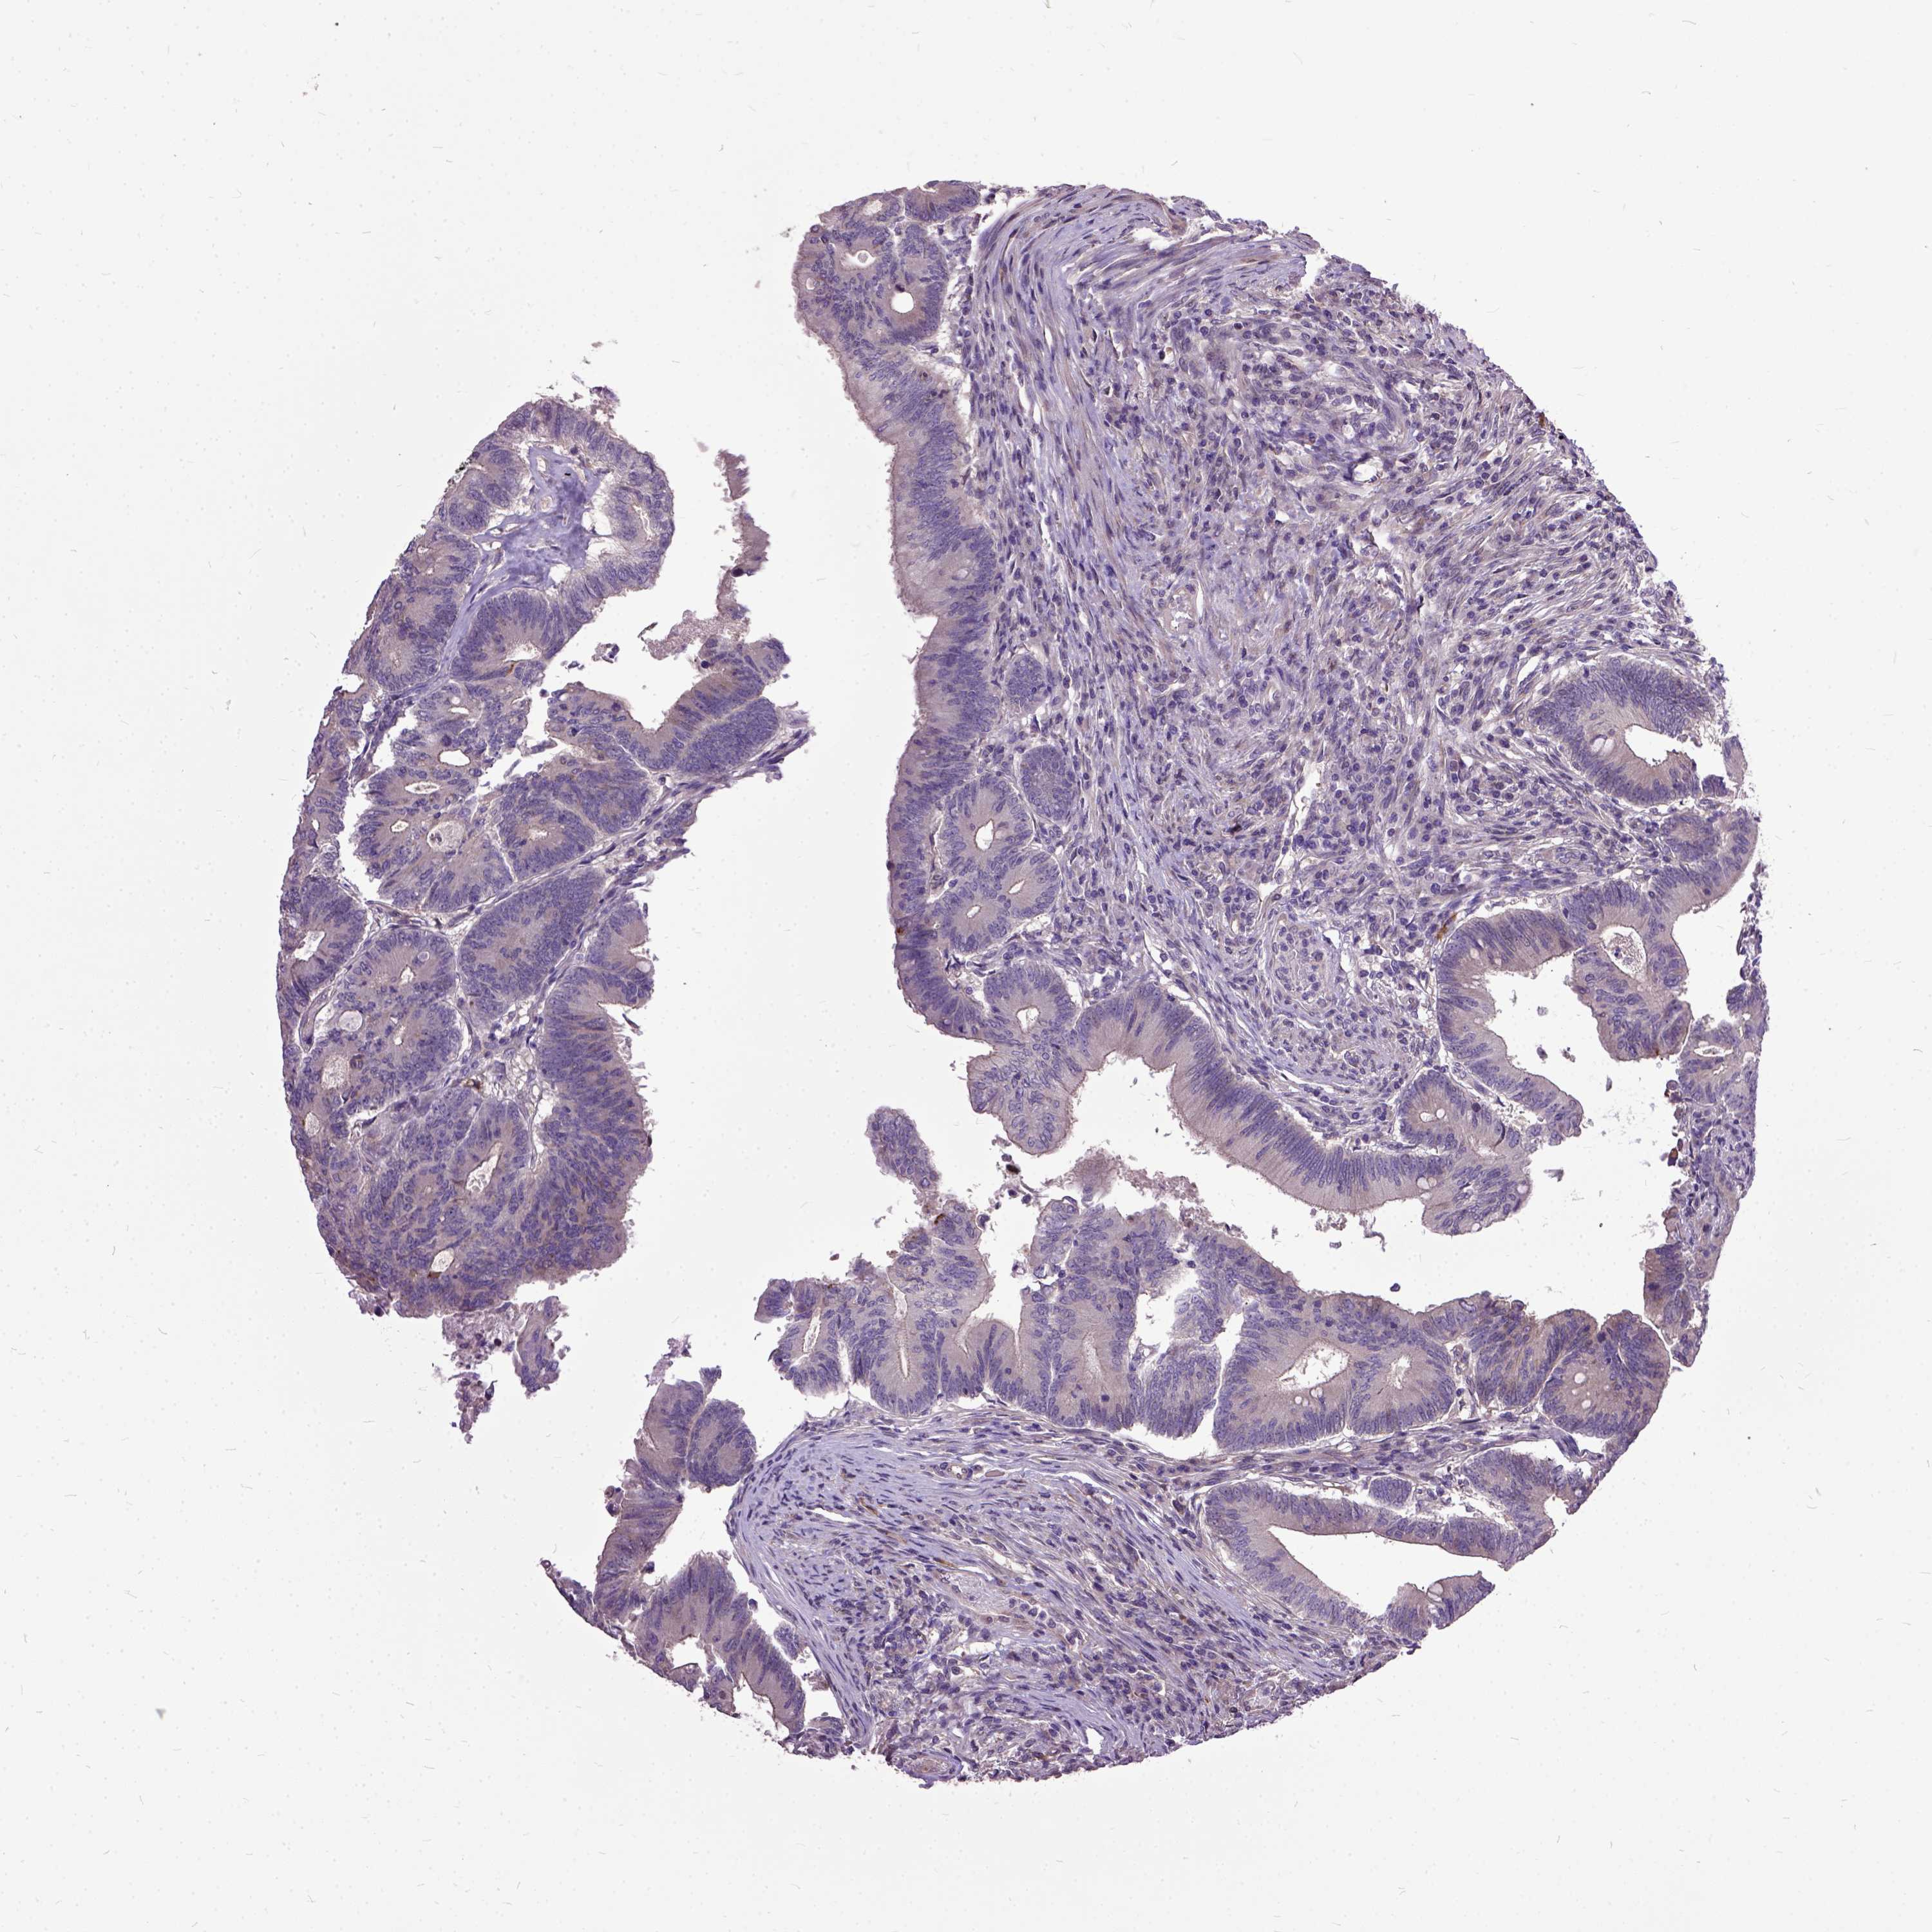

Colorectal cancer

Human cancer

Colon adenocarcinoma

Rectum adenocarcinoma